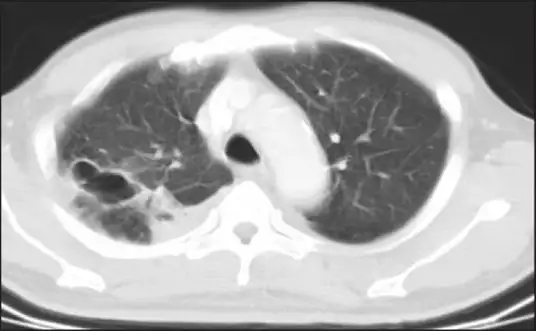

肺部是最常见的战场。类鼻疽肺炎可以表现为急性或慢性,症状从轻微的咳嗽到致命的呼吸衰竭不等。在X光片上,它常常呈现为上叶浸润,有时伴有空洞形成——这种表现与肺结核惊人地相似。许多患者被误诊为结核病,接受了长达数月的抗结核治疗,却毫无效果。

在泰国南部和印度尼西亚班达亚齐的临时医疗帐篷里,幸存者们开始出现奇怪的呼吸道症状。这些患者在海啸中吸入或吞入了大量的浑浊海水,最初几天似乎并无大碍。但在海啸后的第三天到第三十八天之间,他们开始出现高烧、咳嗽和呼吸困难。胸部X光显示多发性的肺部结节和实变,一些患者发展成坏死性肺炎。

当地医生很快意识到,这些症状与类鼻疽完全吻合。海啸掀起的海水和泥浆中含有大量的伯克霍尔德菌,当幸存者们在水中挣扎求生的那一刻,细菌便通过吸入进入了他们的肺部。在一项对泰国南部六名幸存者的研究中,所有患者都表现出肺炎的症状,胸部CT显示多发性的肺部结节和空洞。